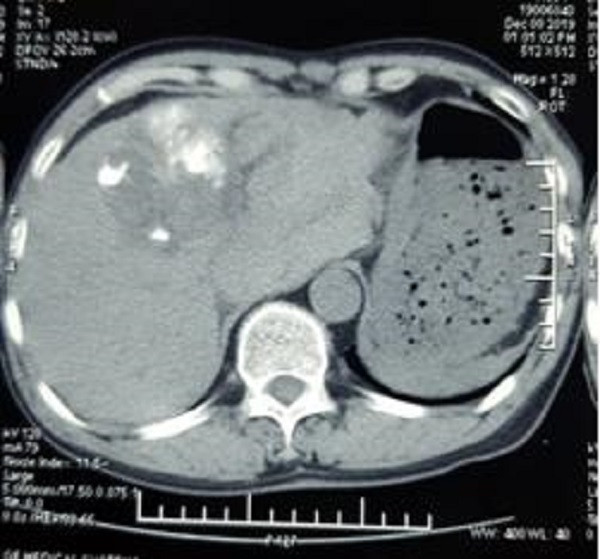

Hình ảnh chụp chiếu cho thấy bệnh nhân bị vỡ u gan

Qua siêu âm, các bác sĩ phát hiện có nhiều máu trong ổ bụng bệnh nhân. Kết quả chụp cắt lớp vi tính cho thấy, khối u gan kích thước hơn 6 cm thâm nhiễm nhu mô gan trái đã vỡ, còn đang có dấu hiệu chảy máu, tạo khối máu tụ lớn khoang hậu cung mạc nối, nhiều dịch máu quanh gan và tiểu khung, chỗ dày nhất 6 cm.